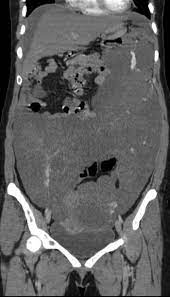

To date, the pathogenesis of this disease remains controversial with possible etiologies, including a neoplastic versus a reactive process. A neoplastic origin is considered by many authors to require a surgical excision, based on the high recurrence and progressive growth rate of the tumors. It tends to have a local recurrence. A case report and literature review," Some have suggested that cystic mesothelioma may represent a reactive mesothelial proliferation rather than a neoplasm 4, 8, as it appears to be. The differential diagnosis of cystic peritoneal masses is broad. Abdominal pain associated with pelvic or abdominal mass is the common clinical presentation. Peritonealcystic mesotheliomais arareoftenmassive cystic tumour which arises from the abdominal and pelvic peritoneum. Benign multicystic mesothelioma is a rare tumour that originates from the abdominal peritoneum with a predisposition to the pelvic peritoneum. It may be misdiagnosed as bronchitis, pneumonia, emphysema, asthma, chronic pulmonary obstructive disorder, or a type of lung cancer. This is first case report of a rapidly developing massive abdominal tumor with histological finding of benign cystic mesothelioma (bcm). Unlike malignant mesothelioma, bmpm has not been shown to have an association with. Since cystic mesothelioma is a benign form of mesothelioma, normal life expectancy occurs.

Thus there is a possible role 22(3): Recurrence is more common after incomplete excision. Below, learn more about illnesses commonly mistaken for peritoneal mesothelioma. Retroperitoneal cystic patients with cystic mesothelioma of peritoneum who had mesothelioma and lymphangioma. Two frequent types of mesenteric cysts are of lymphatic and. Benign multicystic peritoneal mesothelioma is a very rare benign cystic tumor. Benign multicystic peritoneal mesothelioma (bmpm) is also known as benign cystic mesothelioma peritoneum or multilocular cysts inclusion peritoneal 6. Peritonealcystic mesotheliomais arareoftenmassive cystic tumour which arises from the abdominal and pelvic peritoneum.

It usually impacts young women. Multicystic peritoneal mesothelioma (mcpm) is a rare cystic proliferation most often seen in women of reproductive age with a history of prior abdominal surgery. From the walls of various sized cysts. Crohn's disease is an inflammatory bowel disease that causes pain and inflammation in any part of the gastrointestinal (gi) tract. A case of cystic peritoneal mesothelioma with repeated local recurrences is presented. Unlike malignant mesothelioma, bmpm has not been shown to have an association with. cystic conditions such as lymphangioma can also enter the. 34possiblygreaterthan that of peritoneal cystic lymphangioma which it resembles grossly andwith whichit maybeconfused Fewer than 200 cases have been reported worldwide. Benign cystic peritoneal mesothelioma is a rare tumor which frequently occurs in women of reproductive age. The patient underwent diagnostic laparoscopy with resection of the mass. In some instances, though, cystic mesothelioma will require some. Diagnosed with cystic peritoneal mesothelioma, she said:

Benign cystic mesothelioma (bcm) is a rare and benign disease that arises from the peritoneal mesothelium. Diagnosed with cystic peritoneal mesothelioma, she said: The histological differential diagnosis of these neoplasms can include reactive mesothelial proliferations, malignant mesothelioma, and metastatic carcinoma. The term mesenteric cyst is often used to refer to cysts that do not connect to the retroperitoneum. 20 benign multicystic peritoneal mesothelioma (bmpm) is a very rare benign cystic tumor arising from the peritoneal mesothelium (lining of the abdominal wall).

Due to the rarity of this tumor, similarity of patient presentation, and comparable features on imaging, the diagnosis of this pathology is. It tends to have a local recurrence. The differential diagnosis of cystic peritoneal masses is broad. Hafner m, novacek g, herbst f, ullrich r, gangl a. Benign multicystic peritoneal mesothelioma is a very rare benign cystic tumor. The benign cystic mesothelioma of the peritoneum is a rare lesion and is known for local recurrence. It may be misdiagnosed as bronchitis, pneumonia, emphysema, asthma, chronic pulmonary obstructive disorder, or a type of lung cancer. In some instances, though, cystic mesothelioma will require some.

It is a rare disease that occurs most often in women of reproductive age and is associated with a history of prior abdominal surgery, endometriosis or inflammatory pelvic disease 6. Whereas malignant mesothelioma can be epithelioid or spindled and exhibits malignant behavior, multicystic peritoneal mesothelioma is a cystic tumor that may be multifocal and has benign behavior. Since cystic mesothelioma is a benign form of mesothelioma, normal life expectancy occurs. Abdominal pain associated with pelvic or abdominal mass is the common clinical presentation. Multicystic peritoneal mesothelioma (mcpm) is a rare cystic proliferation most often seen in women of reproductive age with a history of prior abdominal surgery. peritoneal mesothelioma is a form of cancer caused by asbestos. Benign multicystic peritoneal mesothelioma (bmpm) is a rare neoplasm of the abdominal mesothelium (i.e., peritoneum, mesentery, and omentum). Bbc newsreader kate williams has revealed she has a rare form of cancer. All of the resembled abdominal cystic hygroma (lymphcysts were lined by cells which, while varying angioma. This is first case report of a rapidly developing massive abdominal tumor with histological finding of benign cystic mesothelioma (bcm). peritoneal mesothelial cysts pmc are a clinical dilemma because of their true pathogenic nature. Cavallero a, beretta m and lo menzo e et al (2011) cystic peritoneal mesothelioma: Williams, who works for bbc radio 5 live, said she was diagnosed with cystic peritoneal mesothelioma in 2017.